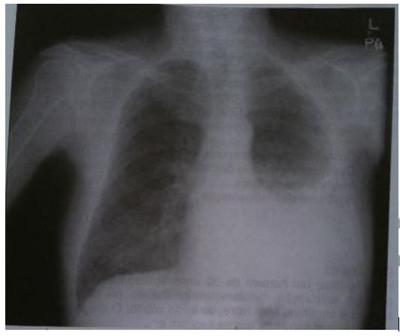

As seguintes alterações podem ser encontradas ao exame físico do paciente cuja radiografia (VER IMAGEM), em correspondência com a área de hipotransparência:

Expansibilidade simétrica e frêmito tóraco-vocal reduzido.

Frêmito tóraco-vocal aumentado, expansibilidade reduzida.

Som maciço à percussão e sons respiratórios aumentados.

Sons respiratórios e frêmito toracovocal abolidos.